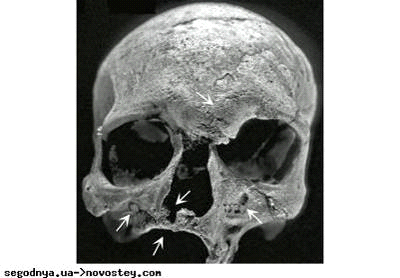

Рентгенограмма рук пораженного. Отлично видны изменения в костях